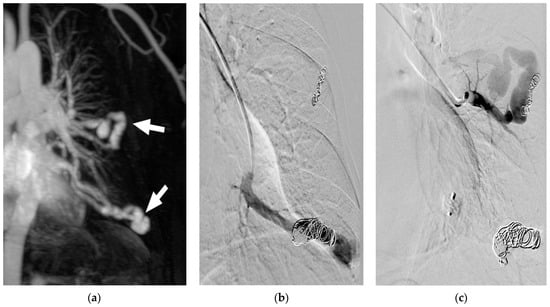

Figure 3. (ac) Re-perfused PAVM after previous treatment elsewhere. Contrast-enhanced MRA (a) shows two large, re-perfused PAVMs (arrows) with early enhancement of the draining vein. In (b) the DSA of one re-perfused PAVM is shown, depicting insufficient dense packing of coils resulting in reperfusion of the vessel. No guide wire should be used, since small thrombi from the coils might be mobilized and lead to systemic emboli. In (c) the second re-perfused PAVM is demonstrated, showing only small coils at the wall of the vessel. Embolization was performed proximal to the treated vessel segment to avoid possible migration of the coils.